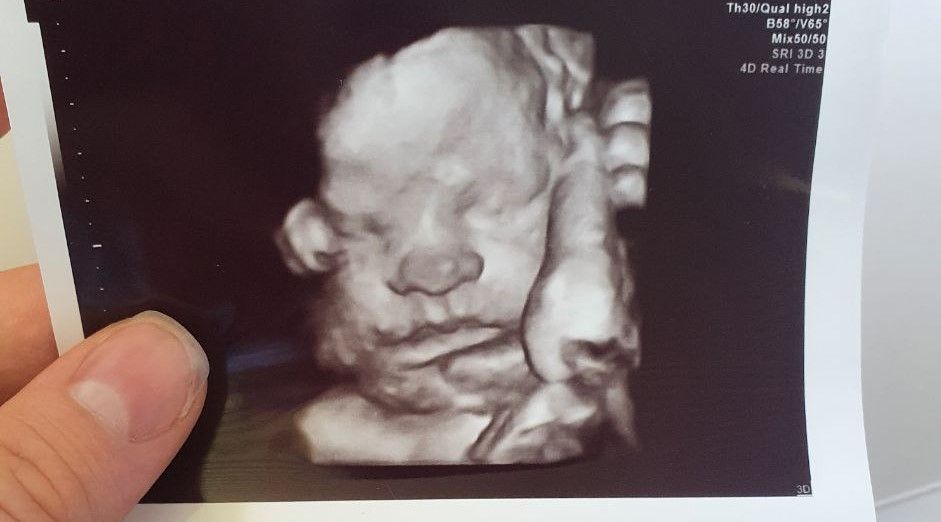

33 неделя. 3 скрининг пройден

Вот и пройден 3 скрининг.

42 сантиметра и 1750 гр. Акробат! Нога у уха)

Пыталась все понять на кого же похож - и все еще не очень ясно)